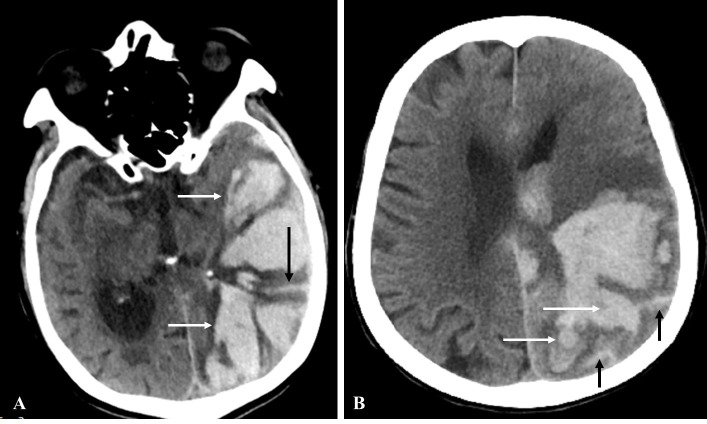

Background and objective: We investigated the association of APOE alleles with CT-based cerebral amyloid angiopathy (CAA) markers including subarachnoid extension (SAE) and finger-like projection (FLP).

Results: 533 patients with supratentorial ICH were enrolled. Among them were 138 patients with lobar ICH and 395 with non-lobar ICH. Compared with the non-lobar group, APOE ε4 (OR 1.894, 95% CI 1.138 to 3.154, p=0.014) and ε2/ε4 (OR 6.098, 95% CI 1.414 to 26.293, p=0.015) were associated with lobar ICH. With regard to CAA markers, APOE ε2 was associated with SAE (OR 2.109, 95% CI 1.167 to 3.810, p=0.013), ε4 was associated with FLP and SAE+FLP (OR 3.026, 95% CI 1.353 to 6.767, p=0.007; OR 3.514, 95% CI 1.485 to 8.316, p=0.004, respectively) and ε2/ε4 was associated with all three factors (SAH: OR 7.599, 95% CI 1.764 to 32.734, p=0.006; FLP: OR 20.333, 95% CI 3.278 to 126.137, p=0.001; SAE+FLP: OR 30.568, 95% CI 4.460 to 209.503, p<0.001) after adjusting for age, and remained significant after adjusting for age and ICH volume.

Conclusion: In patients with spontaneous supratentorial ICH, APOE ε2 and ε4 alleles were associated with SAE and FLP, respectively, suggesting APOE allele-specific effects on CT markers of CAA and their potential mechanisms.